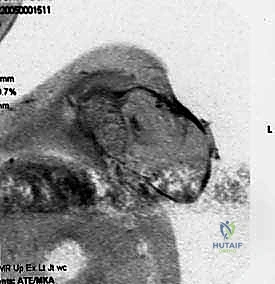

- التصوير الطبي المتقدم: استخدام الرنين المغناطيسي (MRI) لتقييم الأنسجة الرخوة، والأشعة المقطعية (CT scan) للصدر للبحث عن أي نقائل سرطانية (Metastasis)، والتصوير المقطعي بالإصدار البوزيتروني (PET Scan).

الخطوة 4: السيطرة على الأوعية الدموية والأعصاب (الخطوة الأهم)

هنا تتجلى خبرة الدكتور هطيف في الجراحة الميكروسكوبية. يتم كشف الشريان والوريد تحت الترقوة (Subclavian Artery and Vein). يتم ربط هذه الأوعية الدموية الكبيرة وقطعها بحذر شديد لمنع أي نزيف مميت. بعد ذلك، يتم تحديد الضفيرة العضدية (Brachial Plexus) - وهي حزمة الأعصاب الرئيسية - ويتم حقنها بمخدر موضعي قبل قطعها لتقليل صدمة العصب والحد من "ألم الطرف الوهمي" مستقبلاً.